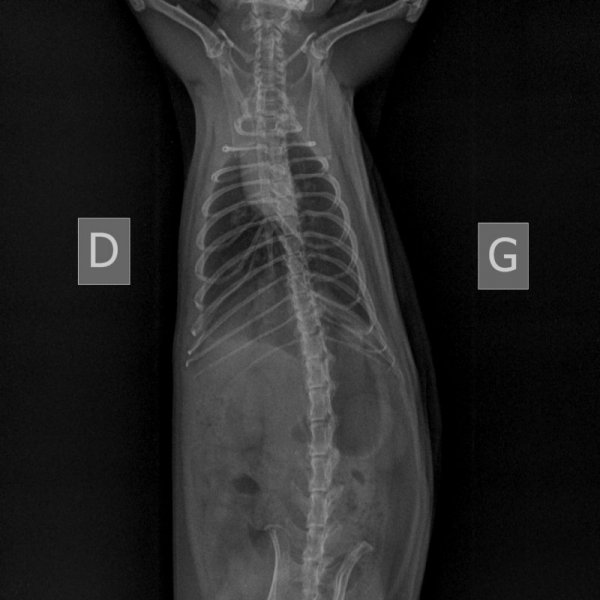

Fin mars j'ai trouvé la respiration de Kobayashi Maru étrange. Elle était un peu plus rapide et superficielle. Dans le doute, j'ai pris RDV pour une radio lundi 4.

Le WE juste avant, il a commencé à faire de légers bruits respiratoire, et sa respiration est devenue clairement plus rapide. À la pesée, je me suis aperçue qu'il avait de nouveau perdu du poids (390g).

À la radio, pour reprendre Artefact "c'est pas si pire", mais ça pourrait être mieux. On trouve quelques foyers. On part avec le véto sur 10 jours de doxycycline, 5mg/kg/12h, en PO.

Les radios d'hier :

NAC-THORAX PROFIL-04_04_2022-14_56_20-547.JPEG

NAC-ABDOMEN FACE NORMAL-04_04_2022-14_56_20-157.JPEG